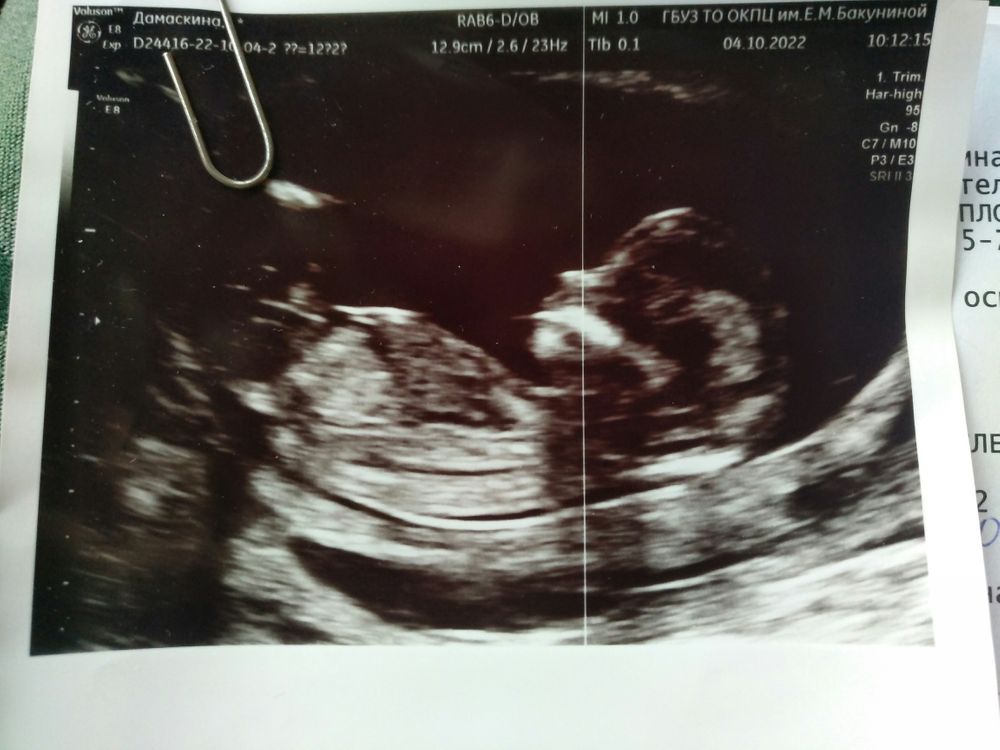

Sabedoria, нет. Пока записана на 9.11 на экспертное УЗИ и амниоцентез. Но генетик сказала, что если эксп. УЗИ будет хорошее прокол никто делать не будет. У меня хгч 103, 7 ме/л ( 3.850 мом) рарр 6.8 ме/ л( 2. 020 мом). Была у двух генетиков и оба говорят, что кровь нормальная. С твп тоже не понятно в заключении 2.7 мм. На на УЗИ сказали все хорошо и ни слова про твп. На фото не понятно...

По фото я бы немножко напряглась- у него пространство в котором вода, видите, почти до половины спинки. По узи если они это посчитают нормой, а носик у него так так есть, то из-за своей халатности и пофигизма могут амнио не назначить🙁